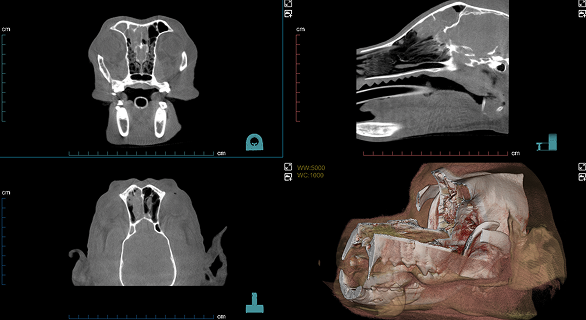

Imágenes Clínicas